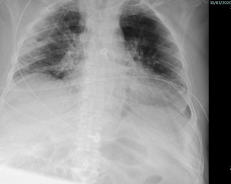

Radiographic findings

พบความผิดปกติจากภาพถ่ายรังสีทรวงอกในวันแรกที่รับไว้ในโรงพยาบาล 66% โดยส่วนใหญ่ที่พบเป็น bilateral peripheral opacities/consolidations (รูปที่ 1) มีส่วนน้อยที่เป็น unilateral involvement (รูปที่ 2) บางรายพบลักษณะของ focal opacities ทำให้ดูคล้ายเป็น nodule หรือ mass (รูปที่ 3) และพบ pleural effusion (รูปที่ 4) เพียง 3 รายเท่านั้น ได้ทำการตรวจ CT scan ไป 4 ราย ซึ่งพบว่ามีความไวในการตรวจพบความผิดปกติได้เพิ่มขึ้น

รูปที่ 4. แสดงภาพถ่ายรังสีทรวงอกธรรมดาของผู้ป่วยติดเชื้อโควิด-19 พบลักษณะ bilateral minimal pleural effusion ในรูปซ้ายมือ และ minimal right-sided pleural effusion ในรูปขวามือ